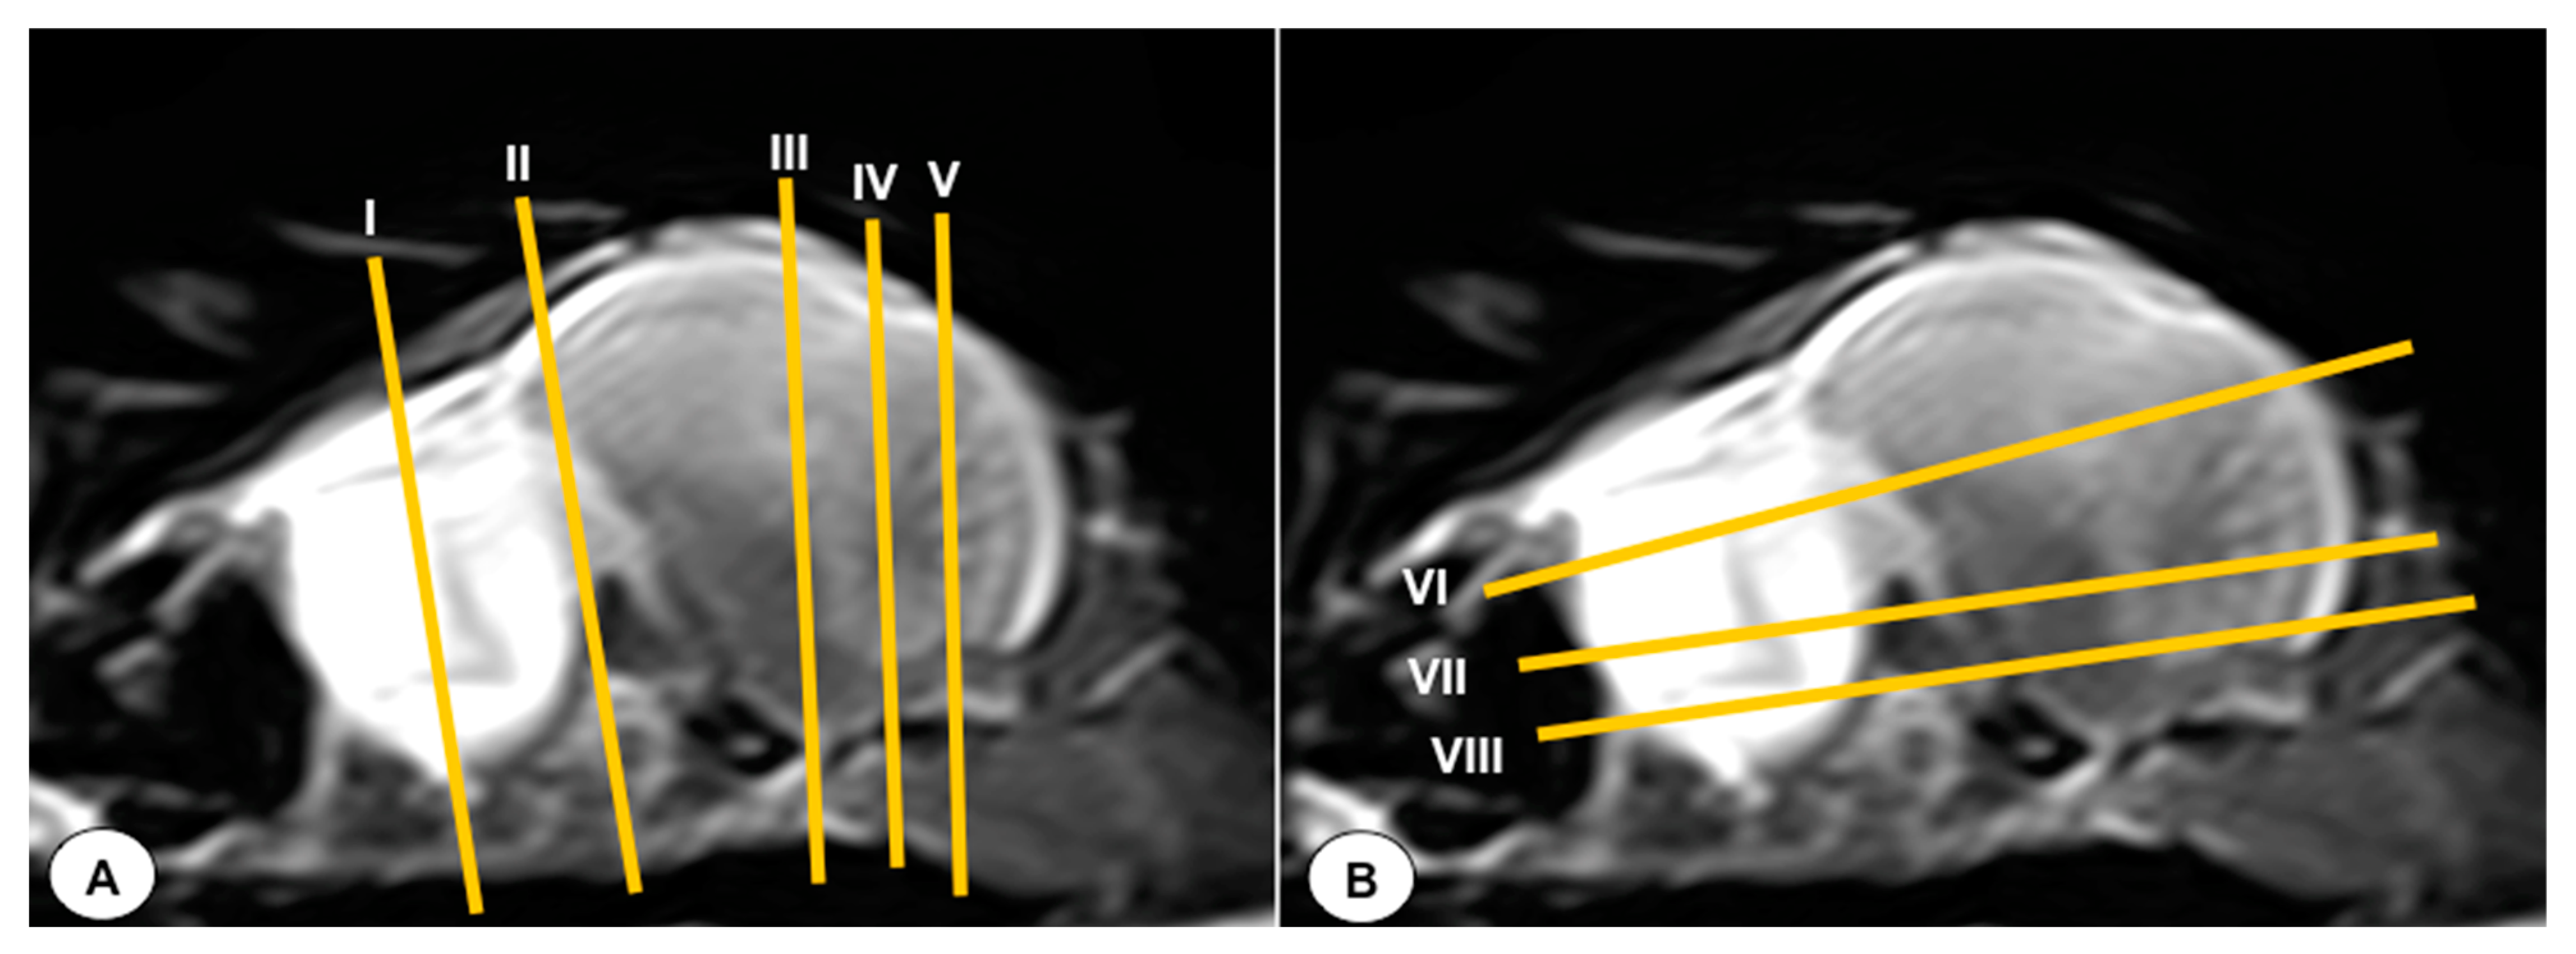

2.2. MRI Technique

2.3. Anatomical Sections